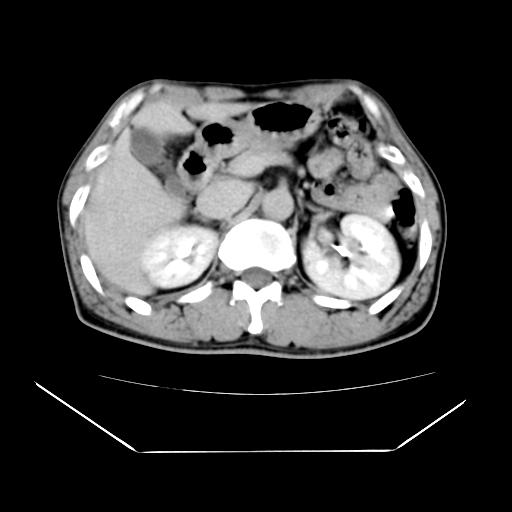

男性,55岁,外院体检afp明显升高,但b超未发现异常,否认乙肝病史。来我院ct增强。有延时扫描。

左肾囊肿.右肺中叶内侧段钙化灶.慢性胆囊炎.

肝脏右叶动脉期可见低密度影,至延迟期被充填,考虑血管瘤可能性大。

不排除肝右叶肝癌可能。

肝6段血管瘤

血管瘤可能性大。

考虑肝右静脉影。